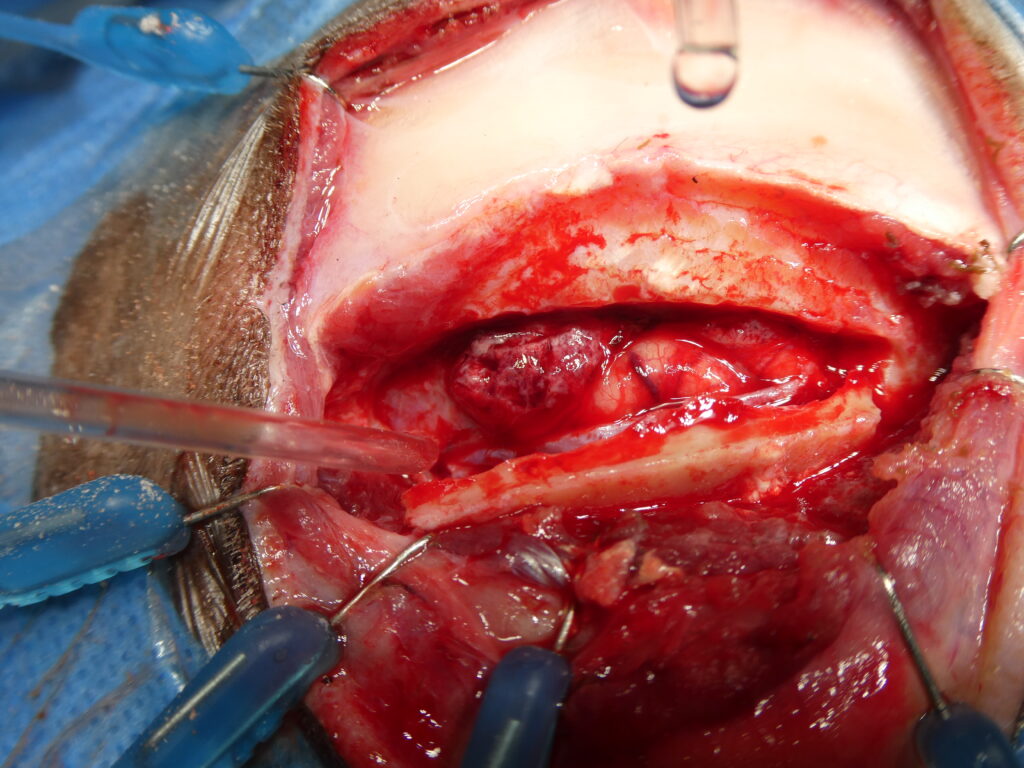

Exérèse d’une tumeur méningée thoracique chez un chat.

L’image centrale illustre l’abord chirurgical peropératoire après exposition de la vertèbre concernée. Une laminectomie ciblée est réalisée afin d’accéder à l’espace épidural et à la lésion. Cette étape requiert une dissection extrêmement minutieuse, dans un environnement anatomique restreint, afin de préserver l’intégrité de la moelle épinière et des structures adjacentes.

L’image de droite montre l’aspect de la tumeur après ouverture osseuse et exérèse. La masse est individualisée puis retirée avec précision, permettant une décompression complète de la moelle épinière. Malgré la sévérité du déficit neurologique préopératoire, l’évolution clinique a été très favorable, avec une récupération fonctionnelle complète du chat après l’intervention, illustrant l’intérêt et l’efficacité de ce type de chirurgie neuro-oncologique lorsqu’elle est réalisée dans des conditions optimales.